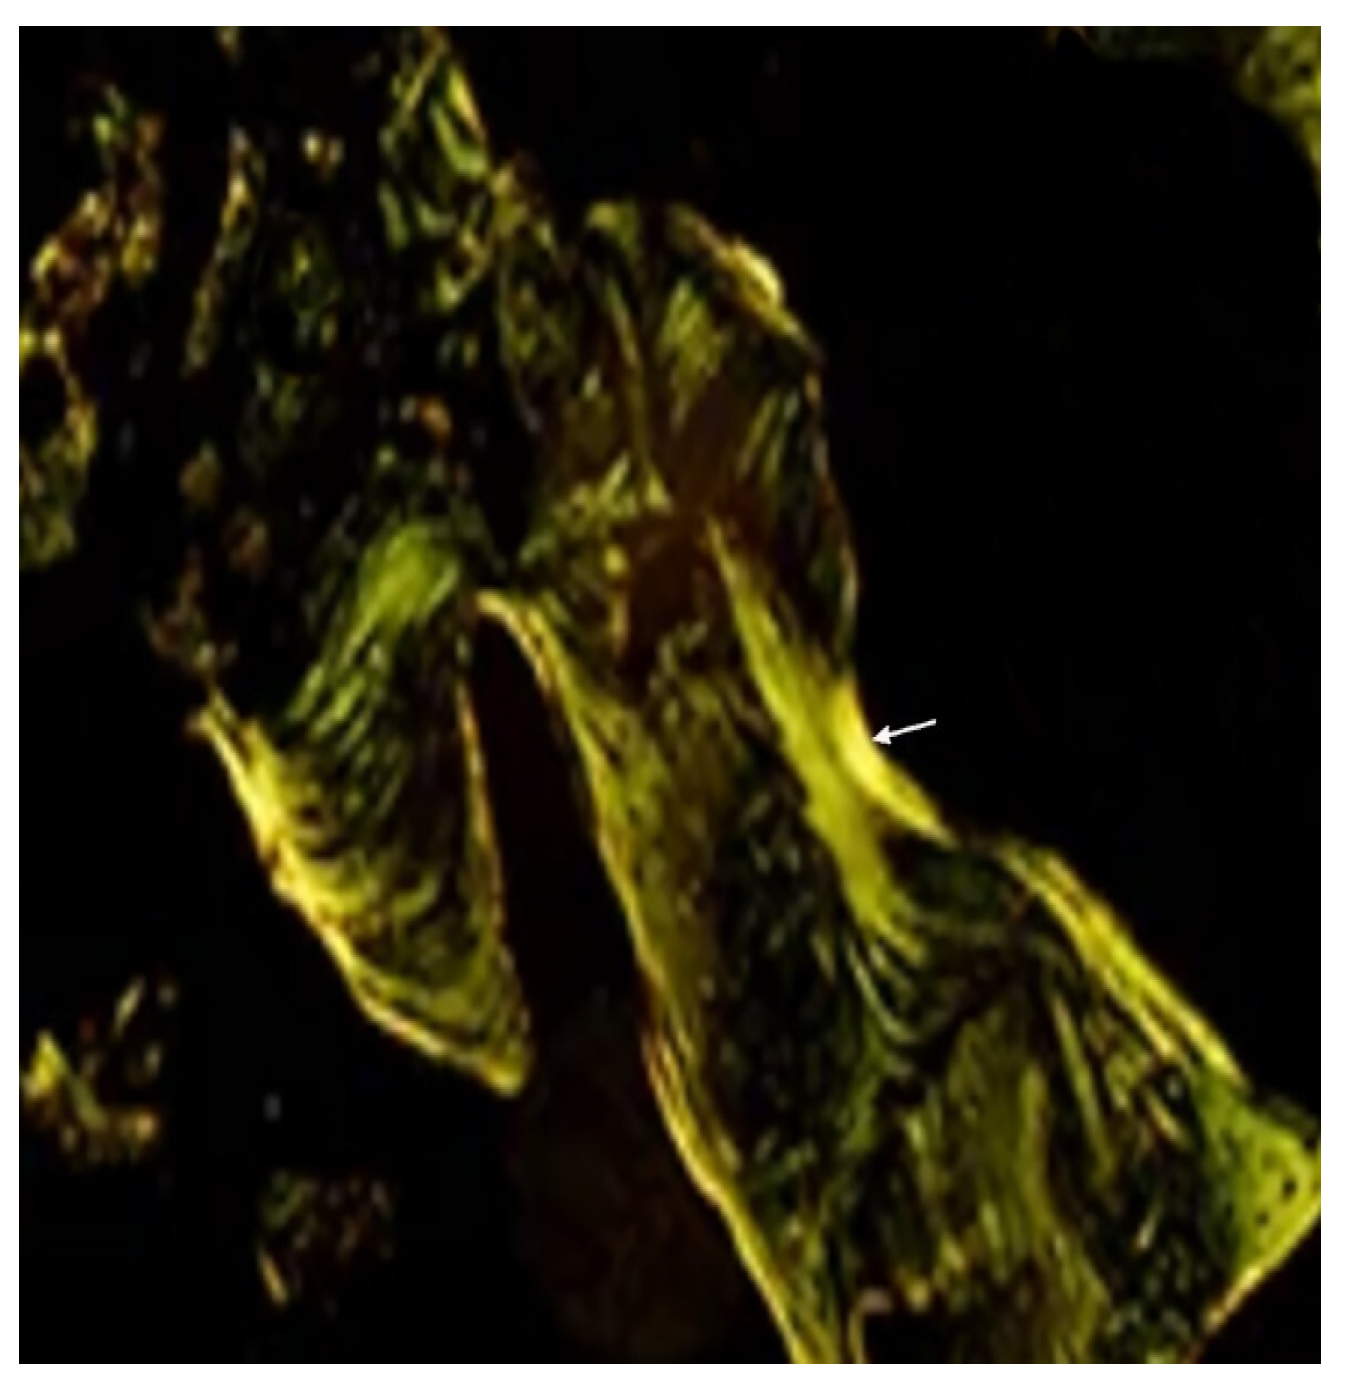

) are recorded. Hematoxylin-eosin staining. Magnification x250.